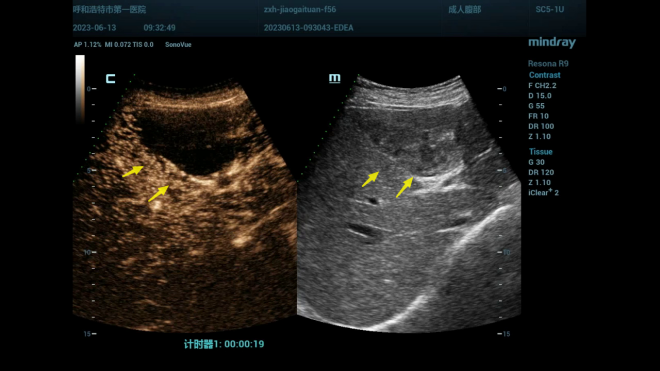

01病例:

老年女性56岁,体检发现肝脏S4段有一中等偏高回声结节,行超声造影检查后考虑血管瘤,手术后证实肝海绵状血管瘤。